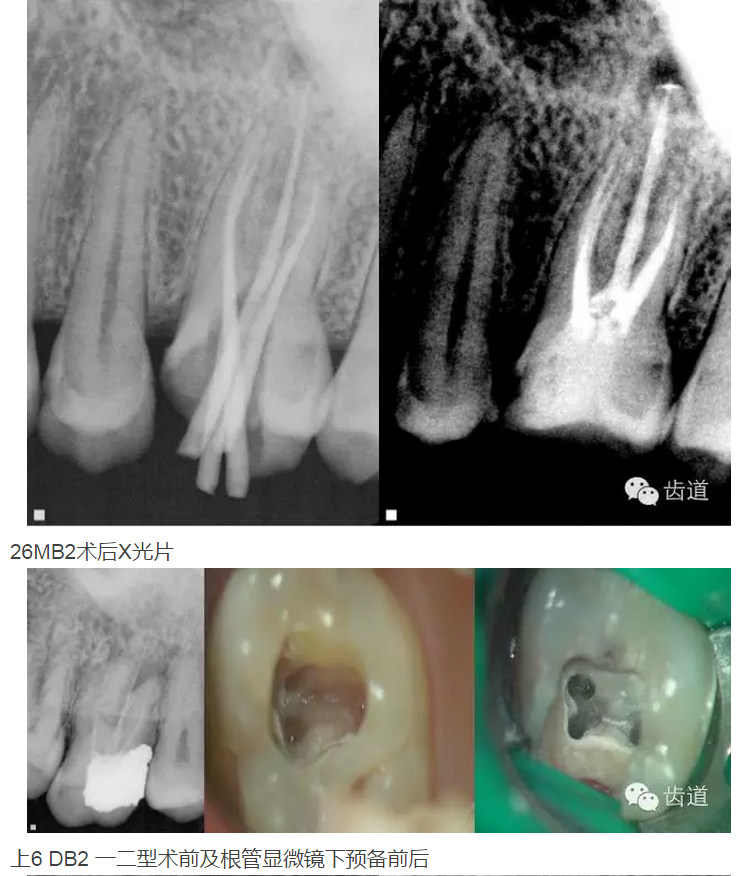

上頜第一磨牙:多為3-4個根管,MB2發(fā)生率約為60%;

上頜第二磨牙:與上頜第一磨牙相似,多為3根管,偶見雙鄂根管;